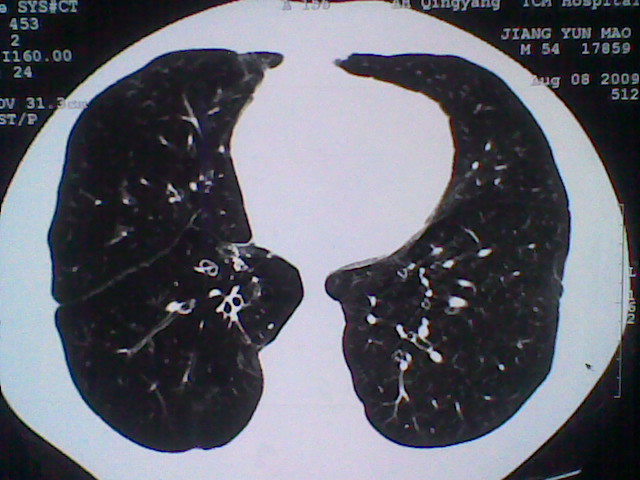

标题: CT21512:支扩伴感染?

患者女。咳嗽数天,咯血半天。

我们报的是支扩伴感染?

支持 支气管扩张并感染。

支持楼主意见,考虑支气管扩张并感染。

支气管扩张并感染。

支持楼主意见,还有肺气肿